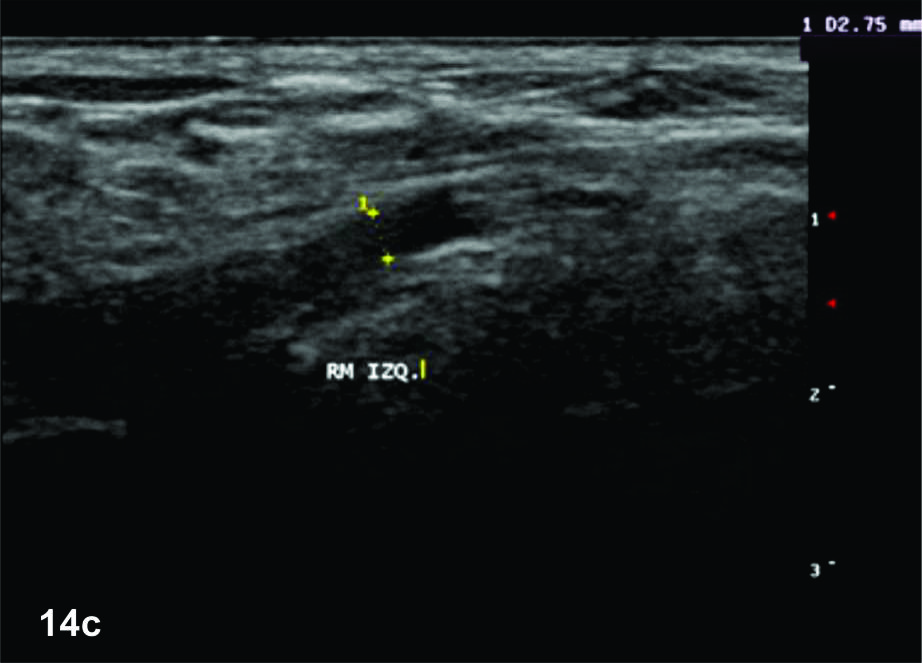

Figura 14 c y d

Lesión traumática del plexo braquial luego de accidente en moto.

C y D- cortes comparativos longitudinales sobre el tronco medio del plexo braquial (C- izquierdo sano y D- derecho patológico), se demuestra la asimetría de la raíz media del plexo, la cual se demuestra en un corte longitudinal comparativo (señalada entre calipers amarillos). La flecha blanca en D señala un fragmento óseo desplazado debido a una fractura del proceso transverso vertebral que generaba conflicto con la raíz.